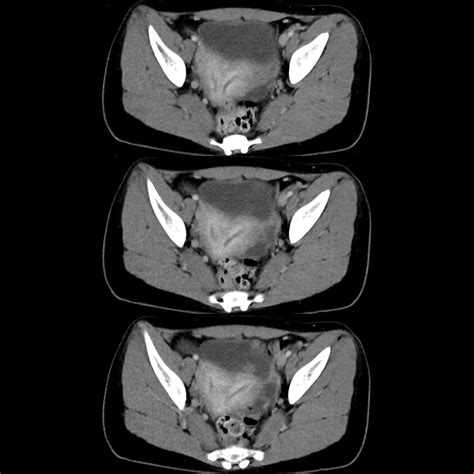

Physicians use advanced imaging to confirm the diagnosis. If you are looking at Didelphic Uterus Images for reference, you will notice the clear separation of the two uterine horns. Common diagnostic tools include:

MRI (Magnetic Resonance Imaging) Detailed anatomical mapping Gold standard for diagnosis